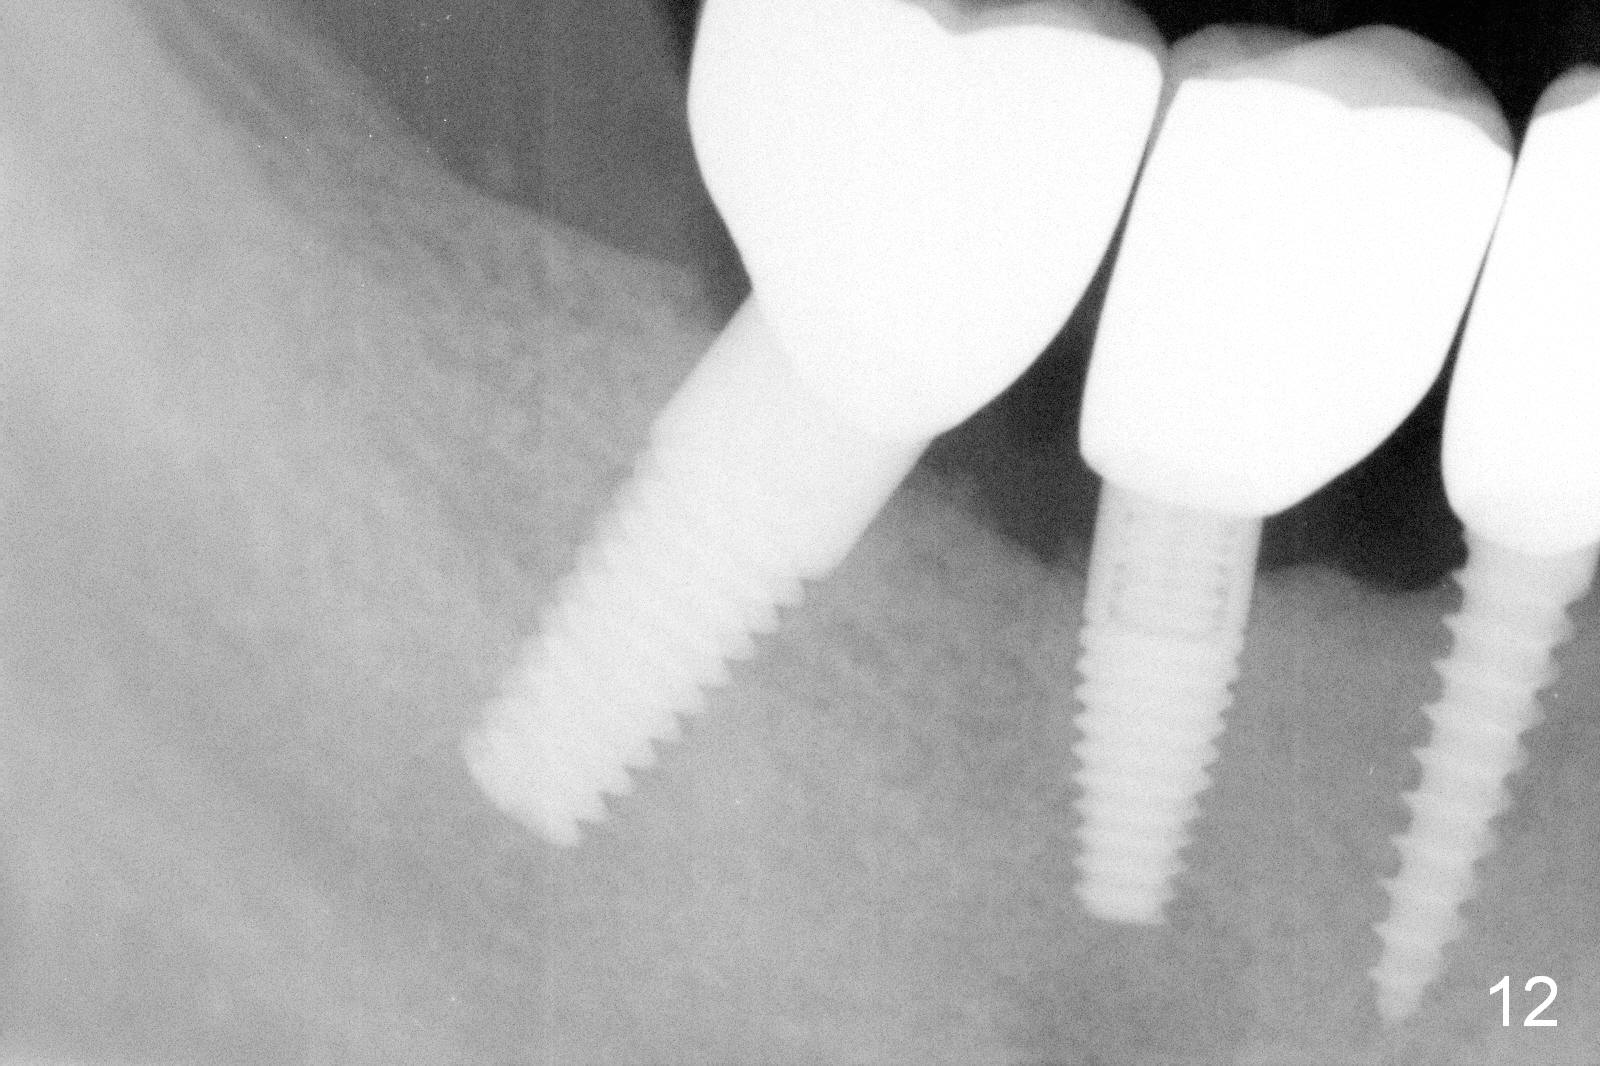

The lower right bridge (from canine (Fig.2: 3) to 1st molar (Fig.1: 6)) fails while a 77-year-old man is undergoing chemotherapy for urinary bladder cancer.  The abutments of the bridge are extracted without plan for implants (Fig.4).   Four months later, the patient returns for implants (Fig.3), but the ridge is narrow (Fig.5).  While 2 of 3x14 mm 1-piece implant are placed at the canine and 1st bicuspid sites, 2 piece ones at the 2nd bicuspid and 1st molar sites (Fig.6: 3.5x11 mm, 5x14 mm).  Soft (Fig.7-10) and hard (Fig.11) tissues heal 1 week (Fig.7) and 4 months (Fig.8-11).  There is minimal bone resorption 1 year 7 months post cementation (Fig.12,13, non-splinting).  It appears that narrow diameter implants are a valid solution to narrow ridge at the sites of the lower canine and premolar.  As long as there are enough implants for function, the crowns are not necessary to be splinted.  Surprisingly, the patient starts flossing after implant restoration.  Retrospectively an immediate provisional bridge should have been fabricated.

There appears to be no bone loss 2 years 5 months post cementation (Fig.14).  Gingival bands form around the implants at #27-29 three years 1 month post cementation (Fig.15 *).